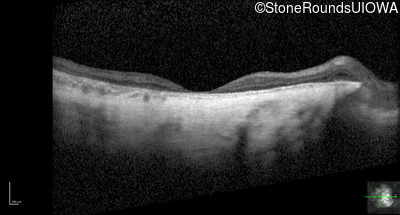

Optical Coherence Tomography - Right - 20/150

Exemplar / OCT Stack